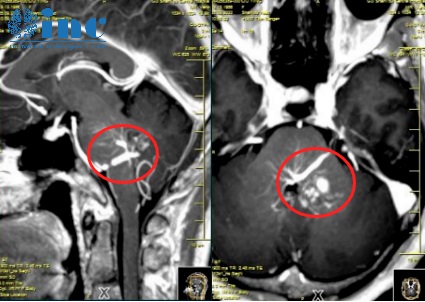

晓玲术前术后影像对比,巴教授全切脑干海绵状血管瘤

术中,INC巴特朗菲教授在苏独墅湖医院医生团队的配合下,凭借丰富的手术经验,避开颅内丰富的血管和神经,清晰地暴露出脑干部位的肿瘤病变,在确定顺利的情况下切除了晓玲的海绵状血管瘤。

手术顺利结束,术中患者生命体征平稳。术后二天,患者即出ICU,无新的神经功能损伤,困扰晓玲的脑干海绵状血管瘤终于切除。